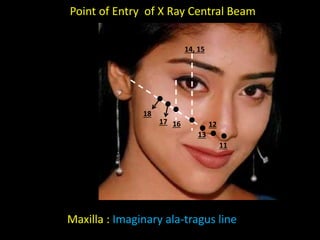

1. The document discusses various intra-oral radiographic techniques including the paralleling cone technique and bisecting angle technique.